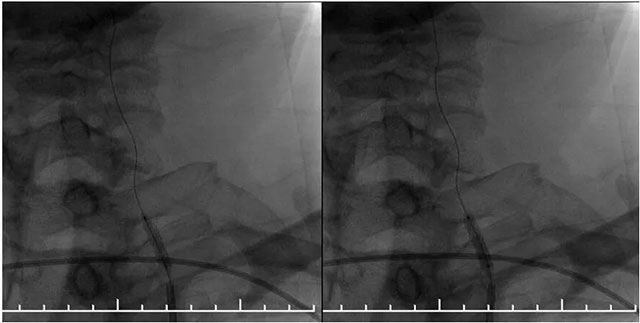

▲ DSA血管造影:左側(cè)椎動脈支架內(nèi)再狹窄

MR示雙側(cè)基底節(jié)區(qū)及右側(cè)頂葉凸面小梗塞(部分軟化灶形成)輕度腦白質(zhì)疏松,MR-tof 可見左側(cè)頸內(nèi)動脈巖骨段狹窄。DSA血管造影:左側(cè)椎動脈支架內(nèi)再狹窄,左側(cè)頸內(nèi)動脈造影見巖骨段遠端狹窄,右側(cè)大腦中動脈由左側(cè)頸內(nèi)部分代償,右側(cè)頸動脈造影提示右側(cè)頸內(nèi)動脈閉塞。